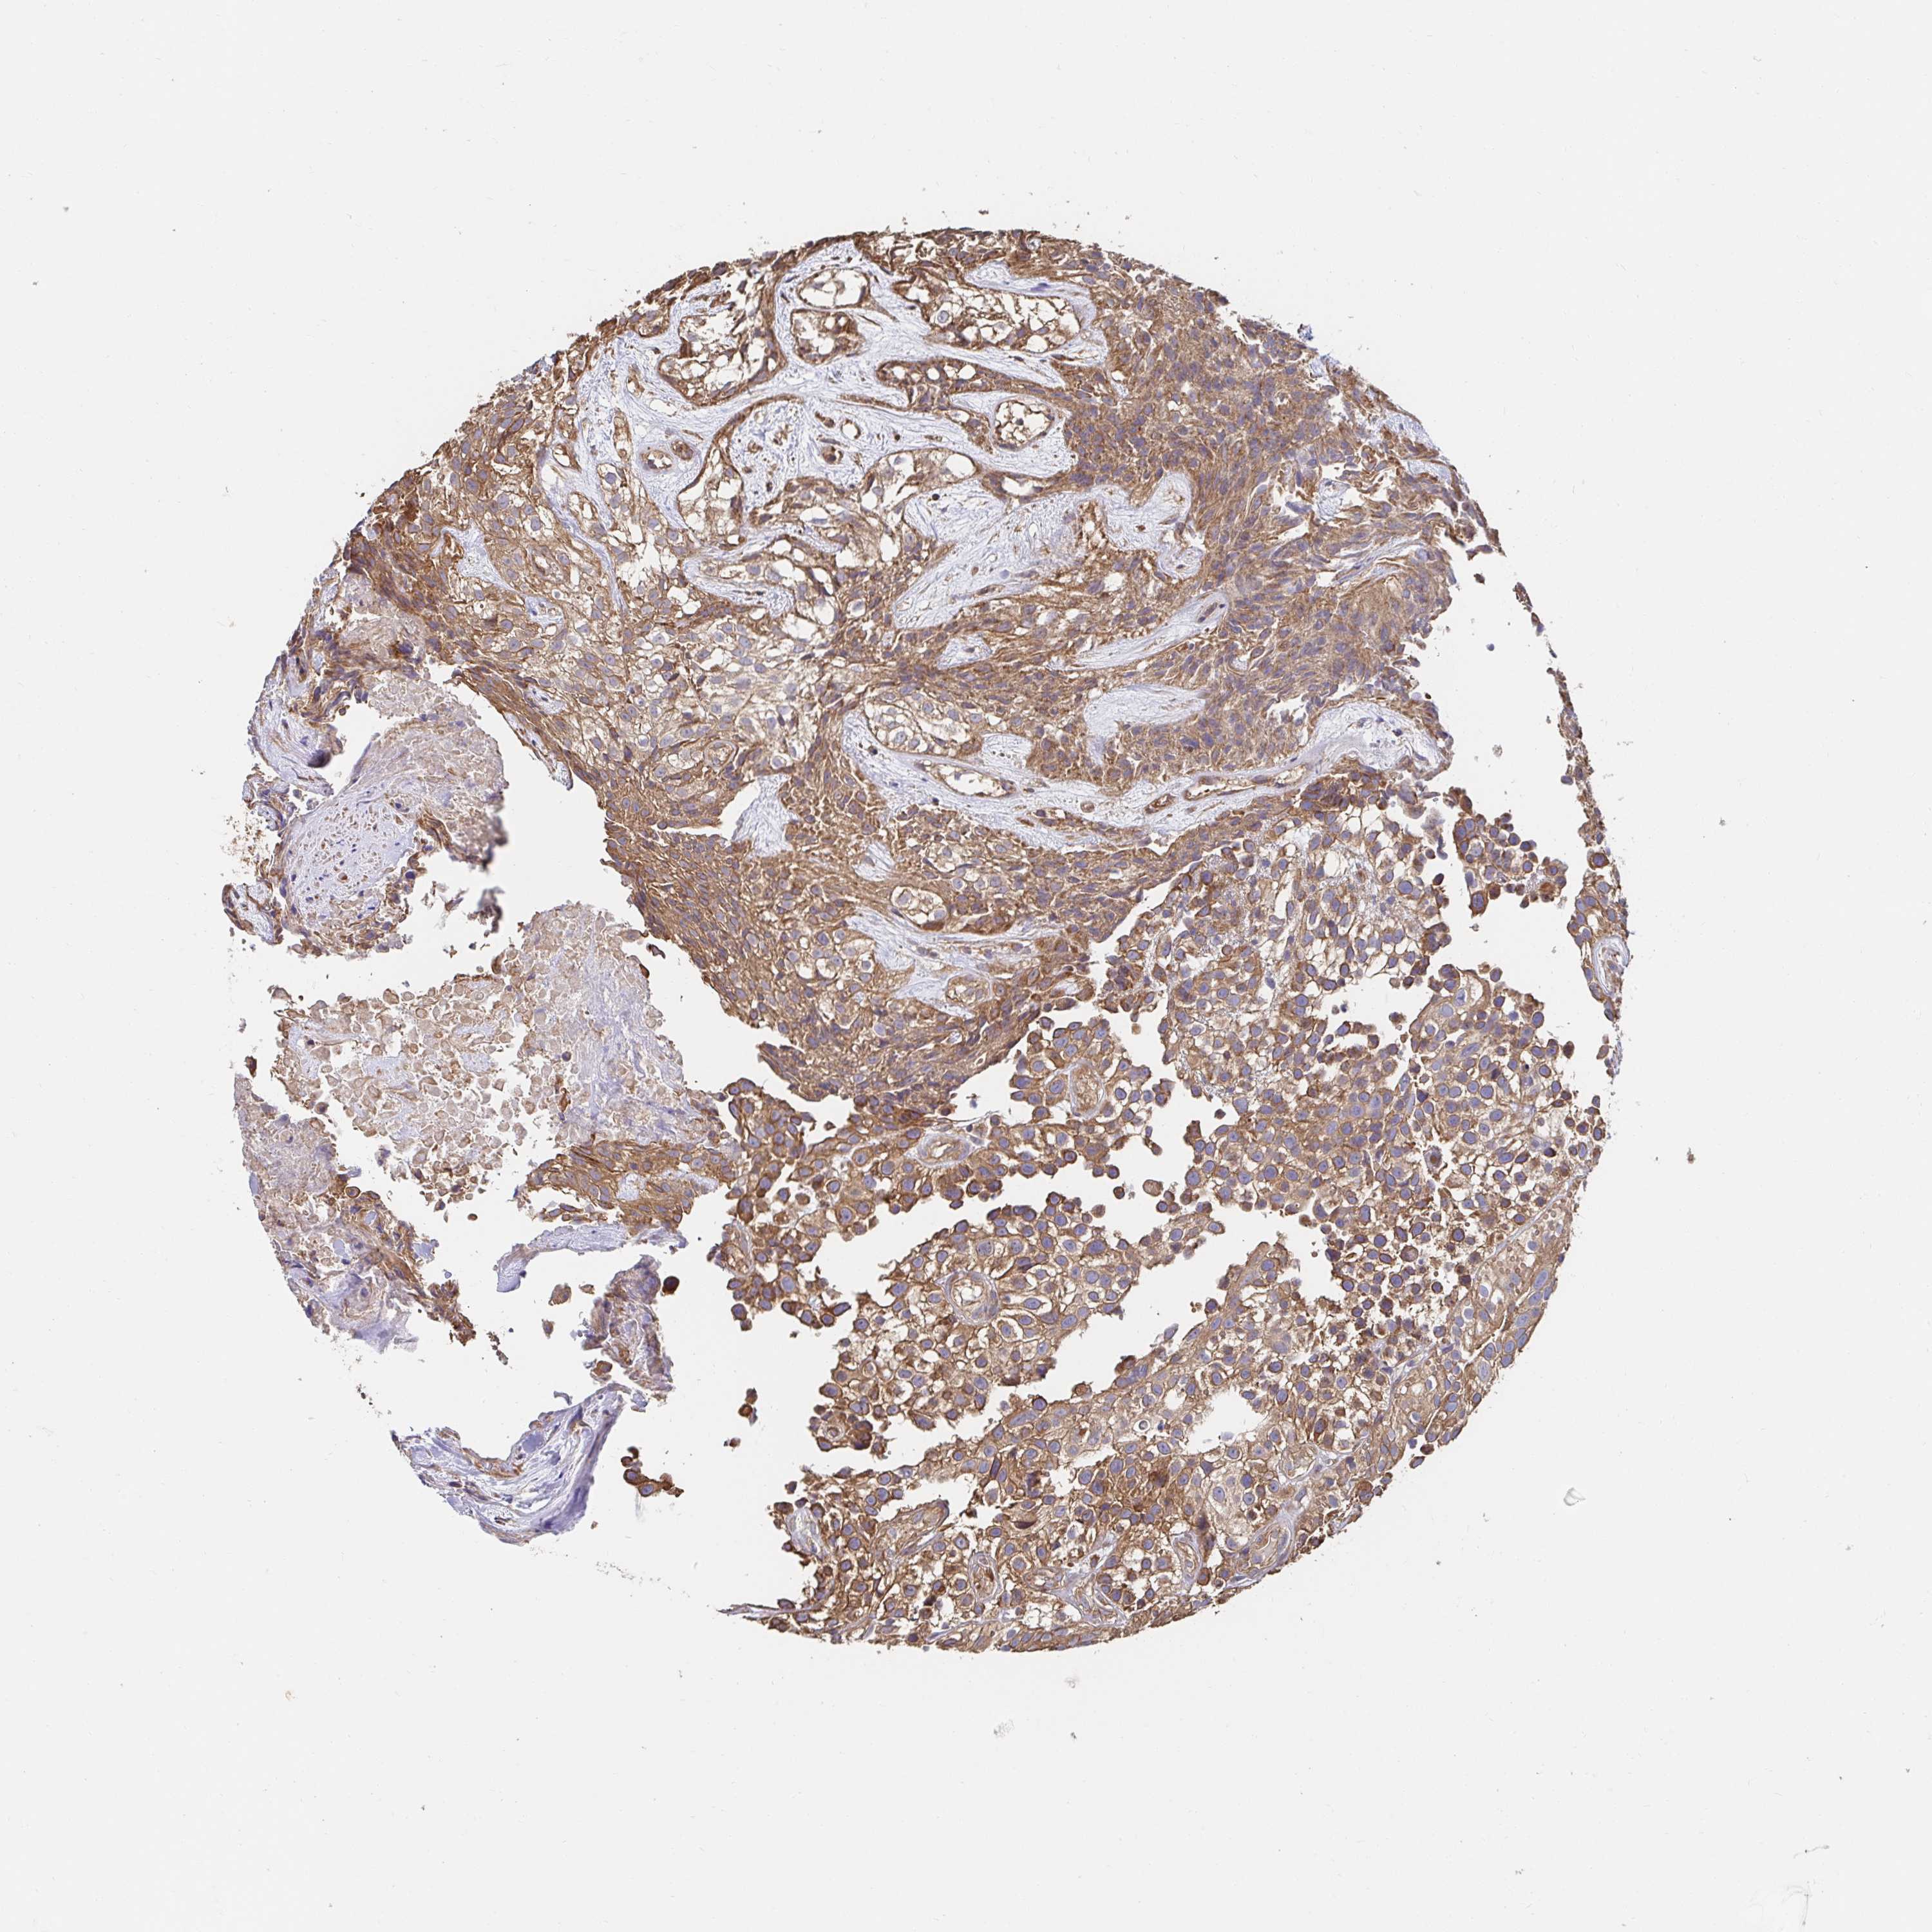

UROTHELIAL CANCER - Protein expressioni

A mouse-over function shows sample information and annotation data. Click on an image to view it in a full screen mode. Samples can be filtered based on level of antibody staining by selecting one or several of the following categories: high, medium, low and not detected. The assay and annotation is described here.

Note that samples used for immunohistochemistry by the Human Protein Atlas do not correspond to samples in the TCGA dataset.

Antibody stainingi

Antibody staining in the annotated cell types in the current human tissue is reported as not detected, low, medium, or high, based on conventional immunohistochemistry profiling in selected tissues. This score is based on the combination of the staining intensity and fraction of stained cells.

Each image is clickable and will lead to virtual microscopy that enables deeper exploration of all samples and also displays staining intensity scores, fraction scores and subcellular localization as well as patient and tissue information for each sample.

Antibody HPA038521

Antibody HPA038522

Staining

High

Medium

Low

Not detected

Intensity

Strong

Moderate

Weak

Negative

Quantity

>75%

75%-25%

<25%

None

Location

Nuclear

Cytoplasmic/membranous

Cytoplasmic/membranous,nuclear

Urothelial carcinoma, High grade

Urothelial carcinoma, Low grade

Urothelial carcinoma, NOS